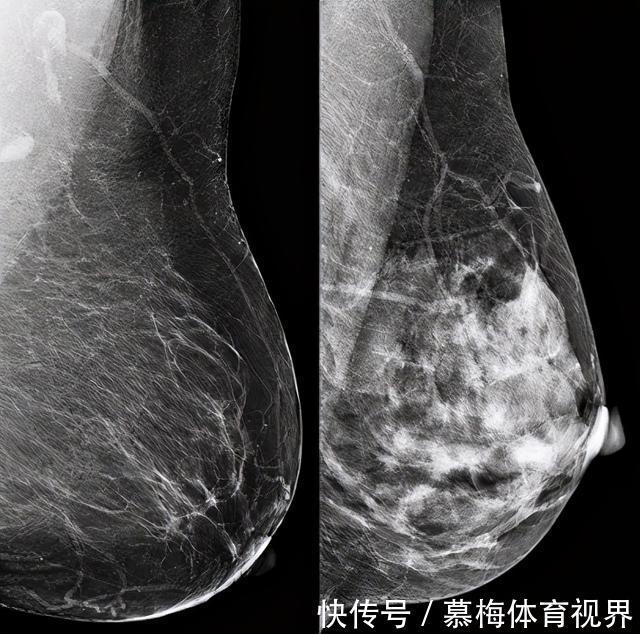

左图为脂肪性乳房右图为致密性乳房什么是乳腺密度通俗讲就是纤维组织+腺体组织与脂肪组织数量的比较而值得注意的是我国有50%以上的女性具有致密型乳腺而致密型乳腺在小胸女性中更为常见所以两相比较胸小的女性可能更容易患癌。不过虽然致密乳腺与乳腺癌的发生风险相关但不是主要的致癌因素单纯讨论胸部大小与患癌风险意义不大。小艾建议大家还是把目光聚焦到乳腺癌的主要致癌因素如遗传因素、肥胖和生活作息紊乱等方面。乳腺癌发生概率和以下因素有关雌激素水平乳腺癌细胞的生长依赖雌激素研究表明女性受雌激素影响的时间越长乳腺癌的风险就越高。对于月经初潮较早、绝经期较晚、晚婚晚育等女性来说由于雌激素水平长期较高乳腺癌风险也较大。遗传因素乳腺癌具有遗传易感性BRCA1/2基因突变会增加乳腺癌的发病率。研究表明有BRCA基因突变的人群一生中罹患乳腺癌的风险高达70%。肥胖肥胖与十几种癌症有关其中就包括乳腺癌。尤其是对于中老年女性来说如果超重或肥胖乳腺癌发病率会增加30%-60%。研究认为主要与肥胖人群雌激素水平和胰岛素水平较高有关。生活作息紊乱经常熬夜或者因为工作因素要上夜班的人长期作息不规律导致生物钟紊乱内分泌失调也会大大增加乳腺癌风险。